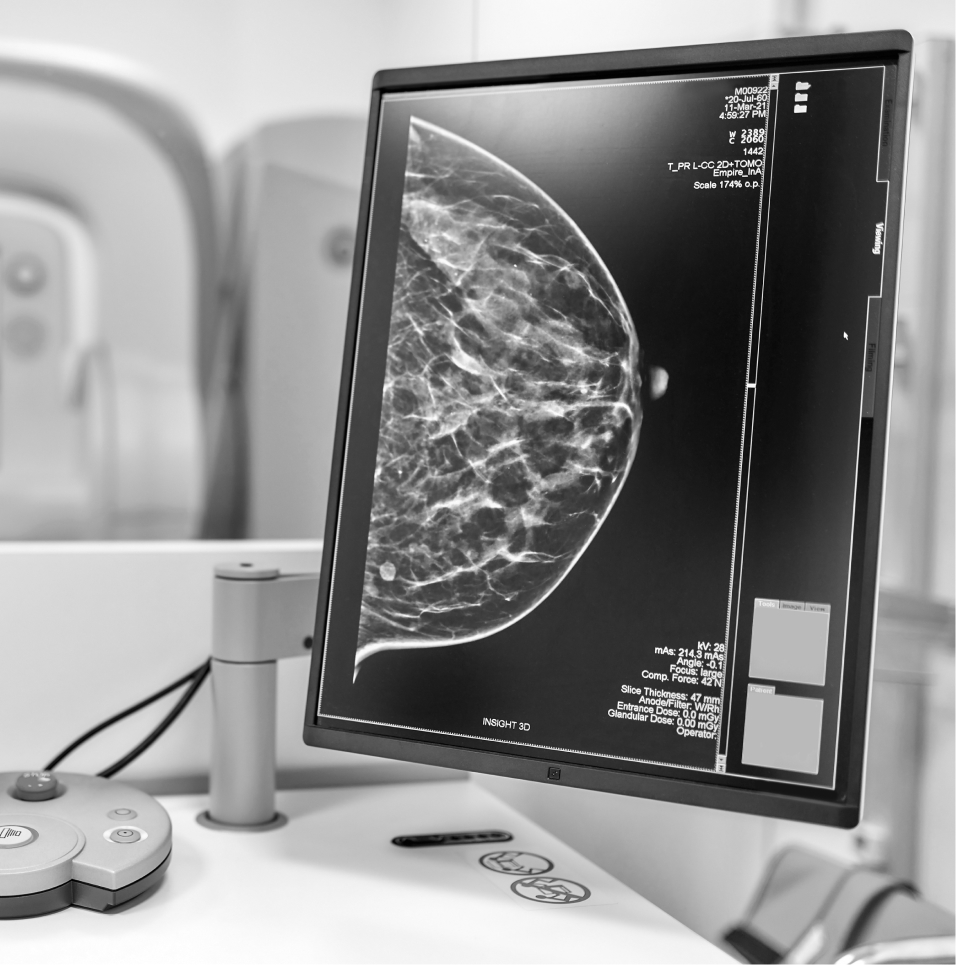

A screening mammogram is a low dose breast X-ray used to detect breast changes that are too small to see or feel during a physical examination. The test usually takes only a few minutes and results are available within a couple of weeks. Depending on your results, further testing may be required which can include a clinical examination by your doctor, a diagnostic mammography (a breast X-ray for women with breast symptoms), an ultrasound, an MRI, or a needle biopsy.

BreastScreen Australia is the national breast cancer screening program that invites women aged between 50 and 74 years to have a free screening mammogram every 2 years. Women between 40 and 49 years, and those over 54 are also eligible to have a free mammogram but will not receive an invitation.